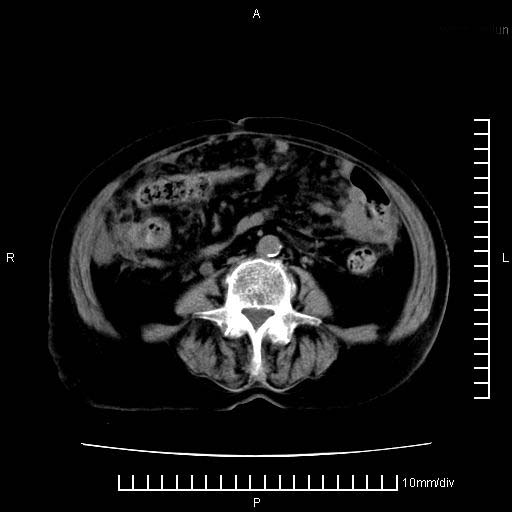

标题: CT28280:腹部增强:女性,80岁

上腹疼痛月余,外院核磁诊断胰腺癌。现临床示右下腹可明显触及包块,可片子上怎么没有看到?

2。腹腔积液。

胰腺体部癌累及周围器官,腹膜、粘连,临床摸到的可能是粘的组织

胰腺结构模糊,胰尾部见囊性包块,周围脂肪密度增高,左肾前筋膜增厚,胸水、腹水。不符合胰腺ca伴腹膜腔转移。考虑胰腺炎伴假性囊肿形成、胸腹腔积液。

右肾盂囊肿。

1)考虑胰腺癌并胰腺假性囊肿形成。2)肝内低密度灶,不排除转移。3)右肾盂积水。4)腹水。5)右侧胸腔积液并右肺下叶部分膨胀不全。

考虑胰腺ca伴腹膜腔转移、肝左叶转移、右肾积水。右胸腔积液。